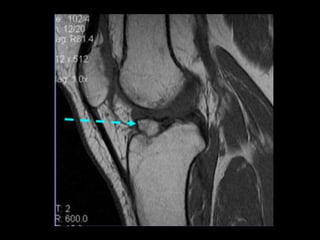

LCA• Rotura completa:

• Mas frecuentes en el extremo

proximal , difícil de visualizar en

sagitales por efecto de volumen

parcial con la cortical del cóndilo

externo. = axiales y cor.

LCA

• Roturas crónicas

• no hay edema ni sinovitis

• pequeño derrame articular.

• LCA no se ve en sagital o coronal

por estar retraído

• LCA puede encontrarse adherido

al LCP falseando el test del cajón

anterior.

• La tibia aparece desplazada

anteriormente respecto al fémur

• Signo indirecto de rotura del LCA:

el aumento de la curvatura o

redundancia del LCP.